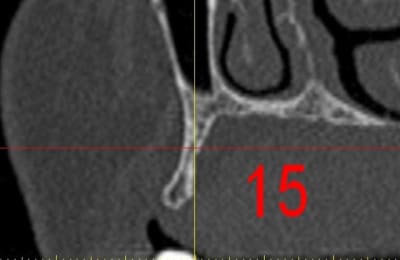

dar15_qsiu0n.jpg

La première diapo est un essai pour justifier le concept (os non destiné à une utilisation greffe)

la deuxième est "tapée" dans une tête de femur de mauvais qualité (rejetée)

la troisième et suivante ce sont "les greffons" définitifs.

Pour la mise en forme de la pièce 1 (appui 12) avec la mise en place, le choix de la tête de fémur, et les discussions pour expliquer la mise en forme, il a fallu 1 h environ, qui pourrait etre réduite à une trentaine de minutes, dans un cas comme celui ci, ce qui est déjà énorme pour l'os d'un patient (mise à nu ect...), sans parler des différents stress.